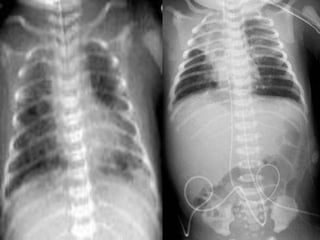

2-Respiratory

Distress

Syndrome

(RDS)

• These infants are typically 34 to 37 weeks of gestation

• RF : include maternal diabetes, multiple births ,Elective

CS , perinatal asphyxia, cold stress, and infants whose

siblings suffered from RDS.

• Because their surfactant sufficiency is borderline and

they have larger pulmonary reserves, affected infants

may be able to cope without ventilation for longer than

smaller preterm infants. Infants who have RDS may do

well with nasal continuous positive airway pressure or

may require ventilation.